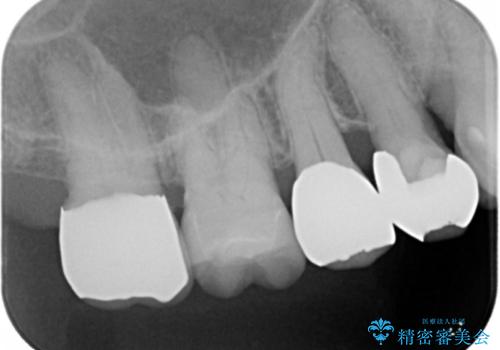

- 奥歯に歯ブラシをあてると痛みがあることを主訴に来院された患者様です。

精査したところ、右上奥の銀歯(右上7)は適合不良により二次う蝕になっていました。

銀歯を外してう蝕を丁寧に除去したのち、オールセラミッククラウンによる補綴治療を行いました。